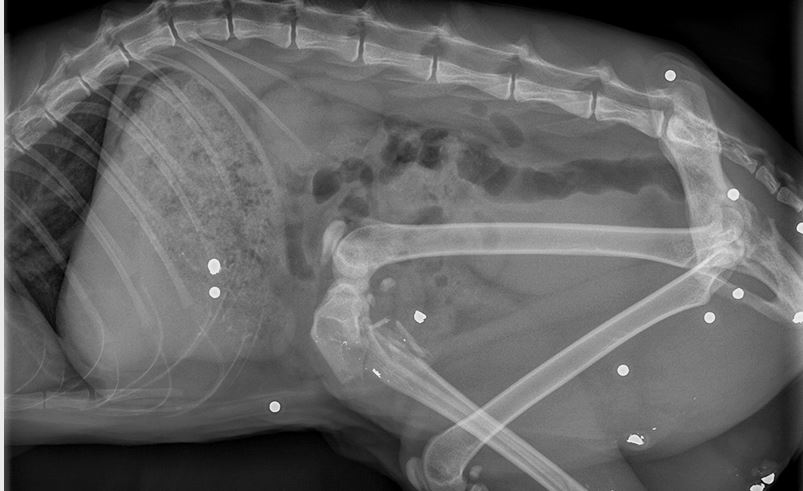

Von 17 Schrotkugeln wurde mutmaßlich in Rockenberg Katze Josi der Familie Krämer getroffen. Das drei Jahre alte Tier war neun Tage nicht nach Hause zurückgekehrt, stand dann am Mittwoch wieder vor der Tür – verletzt am Hinterlauf. In der Gießener Uni-Tierklinik wurde der Bruch diagnostiziert, ein Röntgenbild zeigte, dass sich 17 Schrotgeschosse im Körper befanden. Josi ist operiert und inzwischen wieder zu Hause.